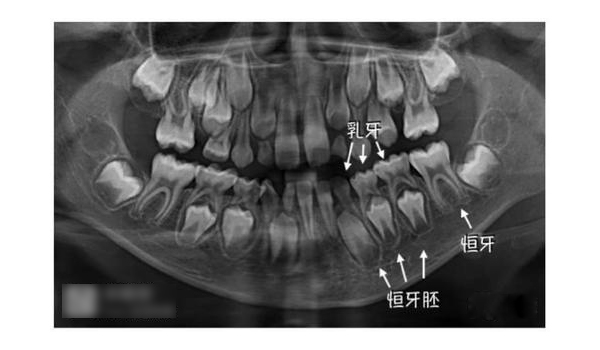

家长不必过分担心宝宝牙齿出得慢。一般要到三岁左右,宝宝的乳牙才会完全出齐。与此同时,恒牙大部分也正在孕育之中。当宝宝步入小学时,会长出第一颗六龄齿。一般等到小学高年级后,乳牙会全部脱落,换上满口的恒牙。但也有的孩子到了中学才换好牙齿。

这是一个误区。健康的乳牙可以保证恒牙的正常发育和引导恒牙正常萌出。乳牙如发育不正常或患龋齿的话,会直接影响到恒牙的发育,如乳牙龋齿特别严重的话,会影响到乳牙牙根根尖部位,甚至下方恒牙的牙胚。因此父母不能掉以轻心,一旦发现龋齿要及时请医生治疗、填补。